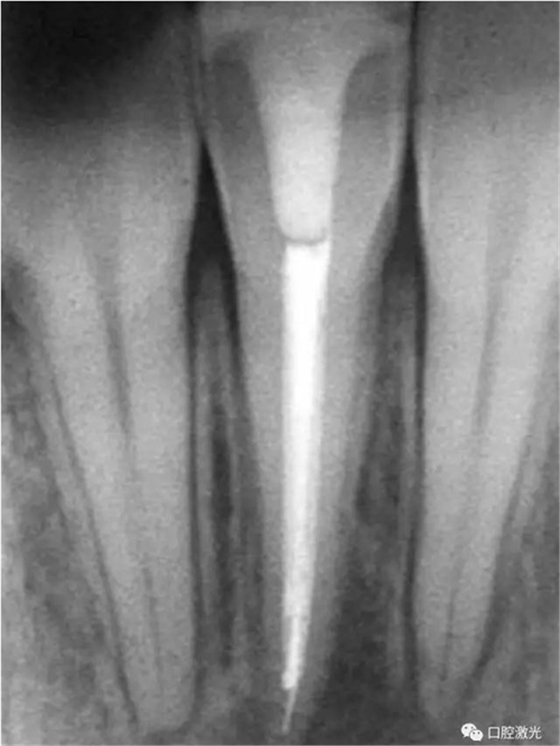

41 治療前X光片

激光治療中

6個(gè)月后治療效果